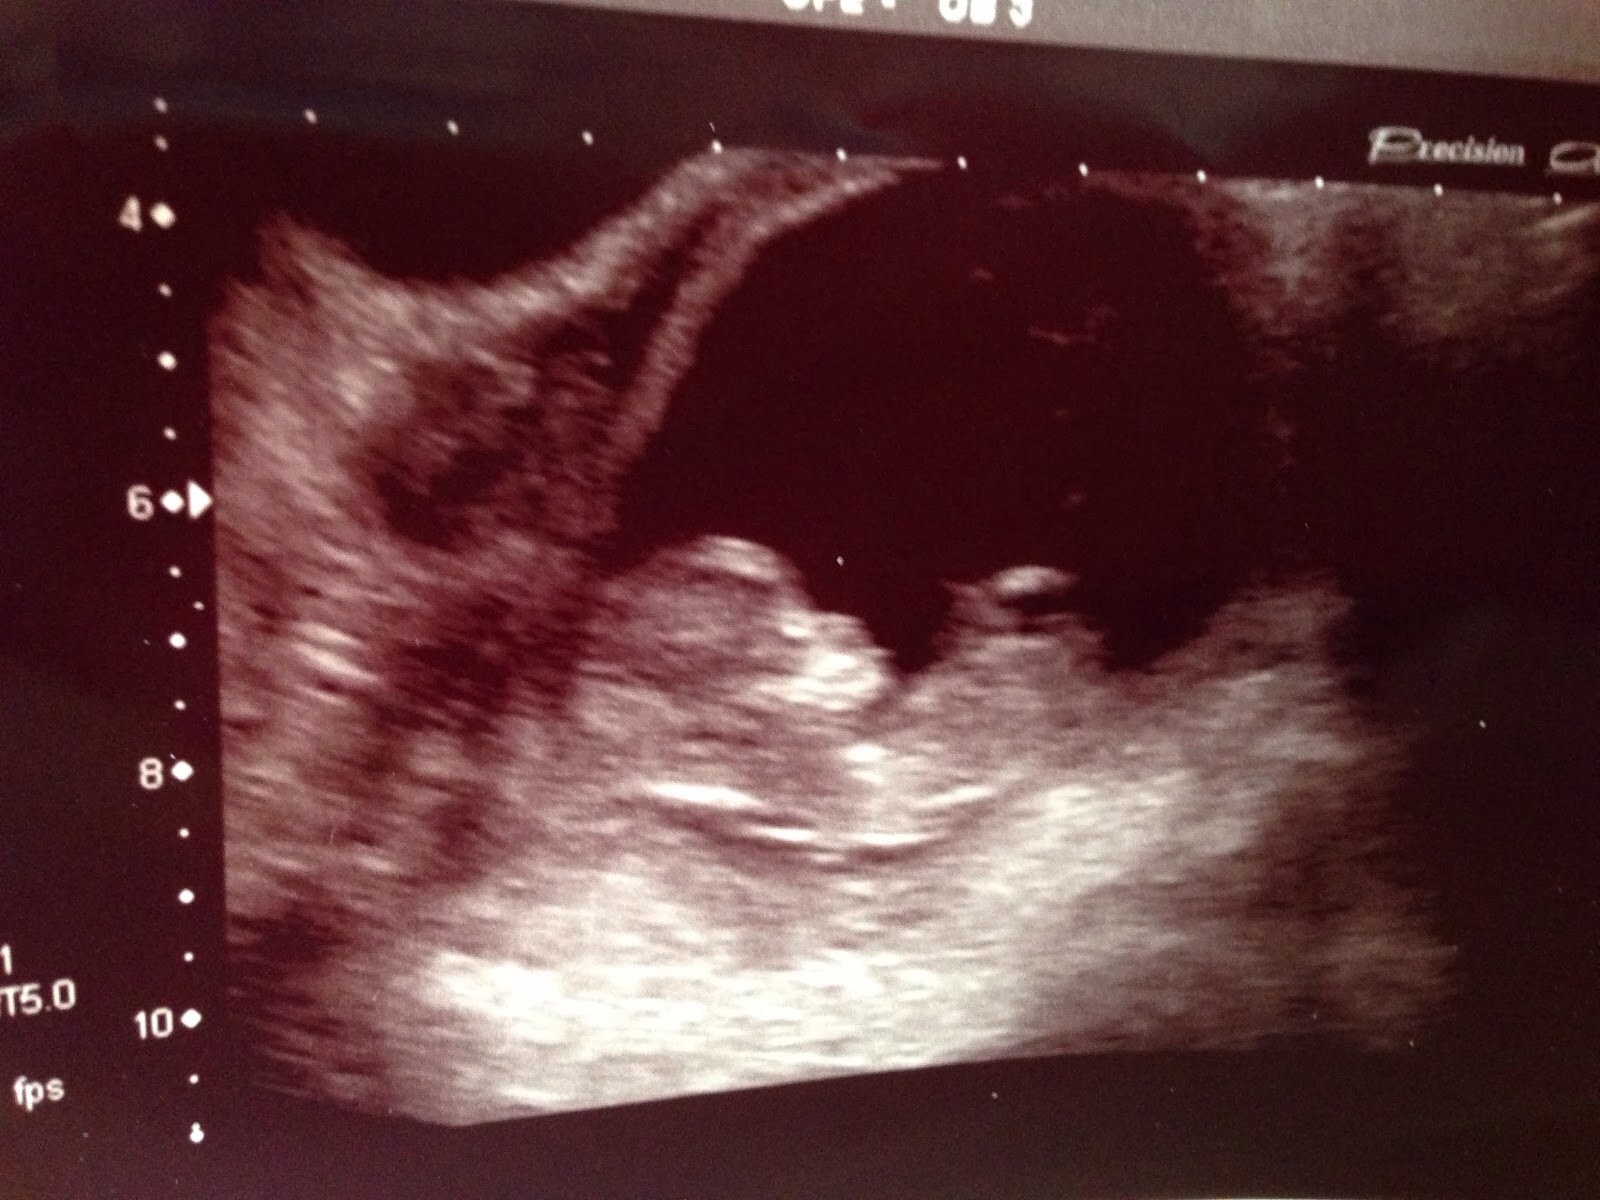

Pic taken 12 weeks. Boy or girl nub?

No nub :(